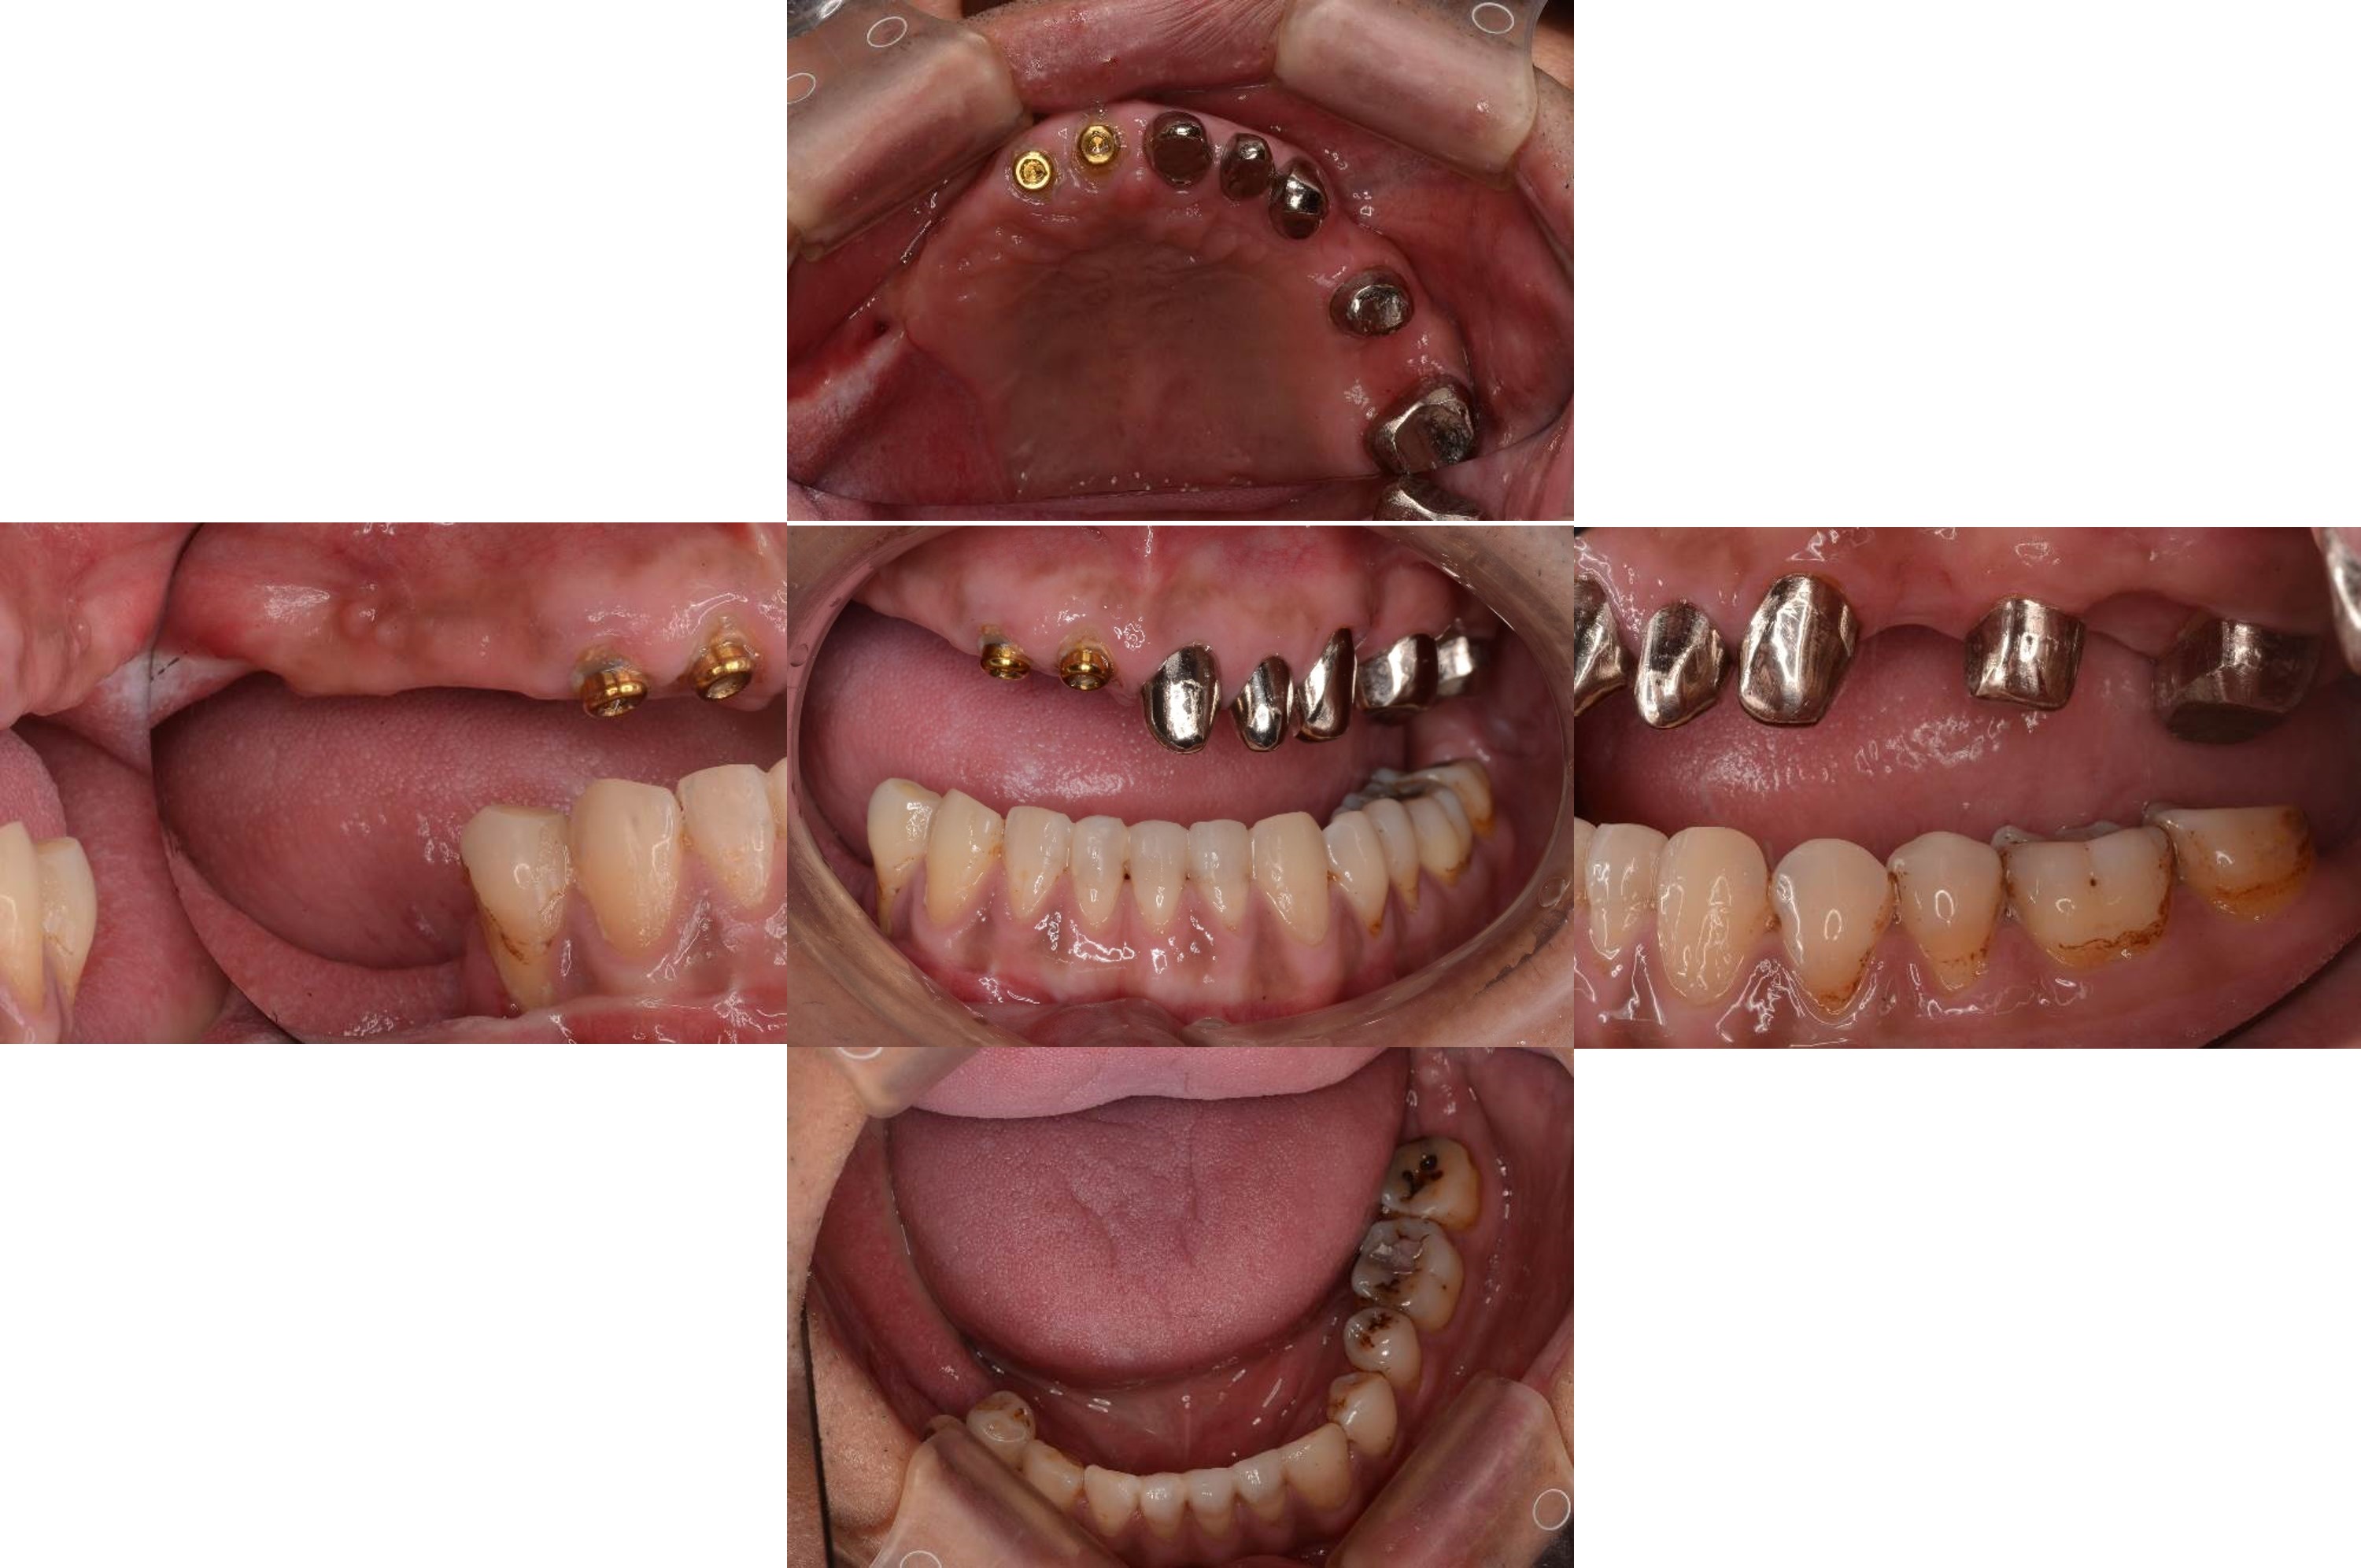

上下顎二階手術

繼續咬合器製作

內冠及定位器口內照

覆蓋型活動假牙

活動假牙口內照